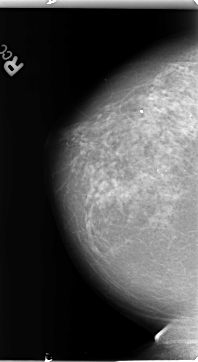

B_3131_1.LEFT_MLO

LEFT_CC LINES 4712 PIXELS_PER_LINE 2632 BITS_PER_PIXEL 12 RESOLUTION 50 OVERLAY

FILE: B_3131_1.LEFT_CC.OVERLAY

TOTAL_ABNORMALITIES 1

ABNORMALITY 1

LESION_TYPE CALCIFICATION TYPE PLEOMORPHIC DISTRIBUTION CLUSTERED

ASSESSMENT 4

SUBTLETY 3

PATHOLOGY BENIGN

TOTAL_OUTLINES 1

BOUNDARY